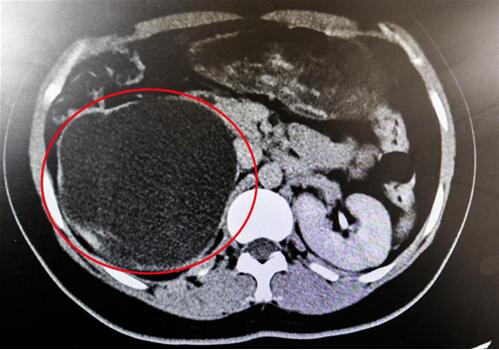

紅圈部分為手術(shù)后腎臟輪廓逐漸清晰。院方供圖

終于,功夫不負有心人,他們在粘連嚴重的腹膜外組織中找到了輸尿管!當時,靳文生主任心里緊繃的一根弦終于松了下來,接下來的手術(shù)過程也變得順暢了。

“雖然耗費了很多時間,但好在結(jié)局非常成功!苯纳魅握f,能為患者保住腎臟,花費再多時間也覺得值得。